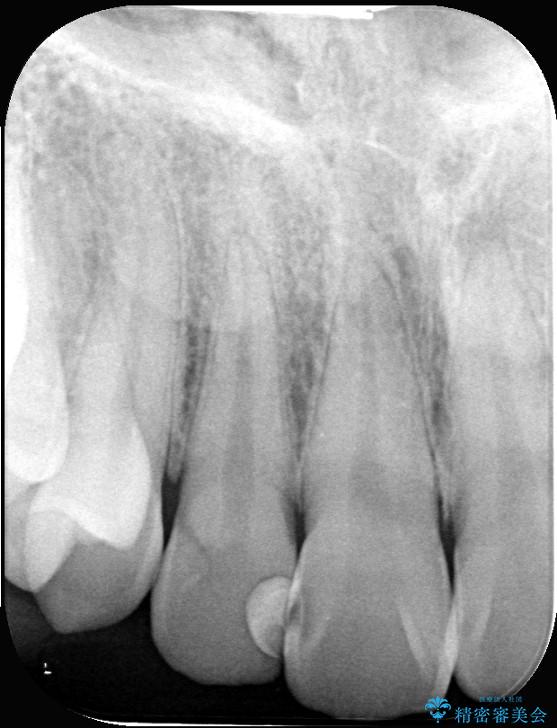

右上2番の歯に自発痛を認め、症状や歯髄診・レントゲン像から不可逆性歯髄炎と診断し、精密根管治療から歯冠補綴まで行うこととなりました。

初診時に歯髄診断を行い、不可逆性歯髄炎と診断し抜髄から補綴修復までの流れを説明し、精密根管治療、ファイバ-コア築造、オールセラミッククラウン(St)修復を行うこととしました。